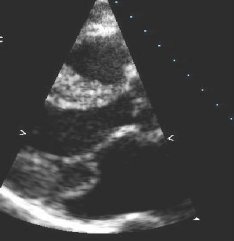

Caused by systolic anterior motion of the mitral valve.[Figure caption and citation for the preceding image starts]: Apical 3-chamber view of hypertrophic cardiomyopathy with systolic anterior motionFrom the collection of Samir Kapadia and Mehdi H. Shishehbor [Citation ends].